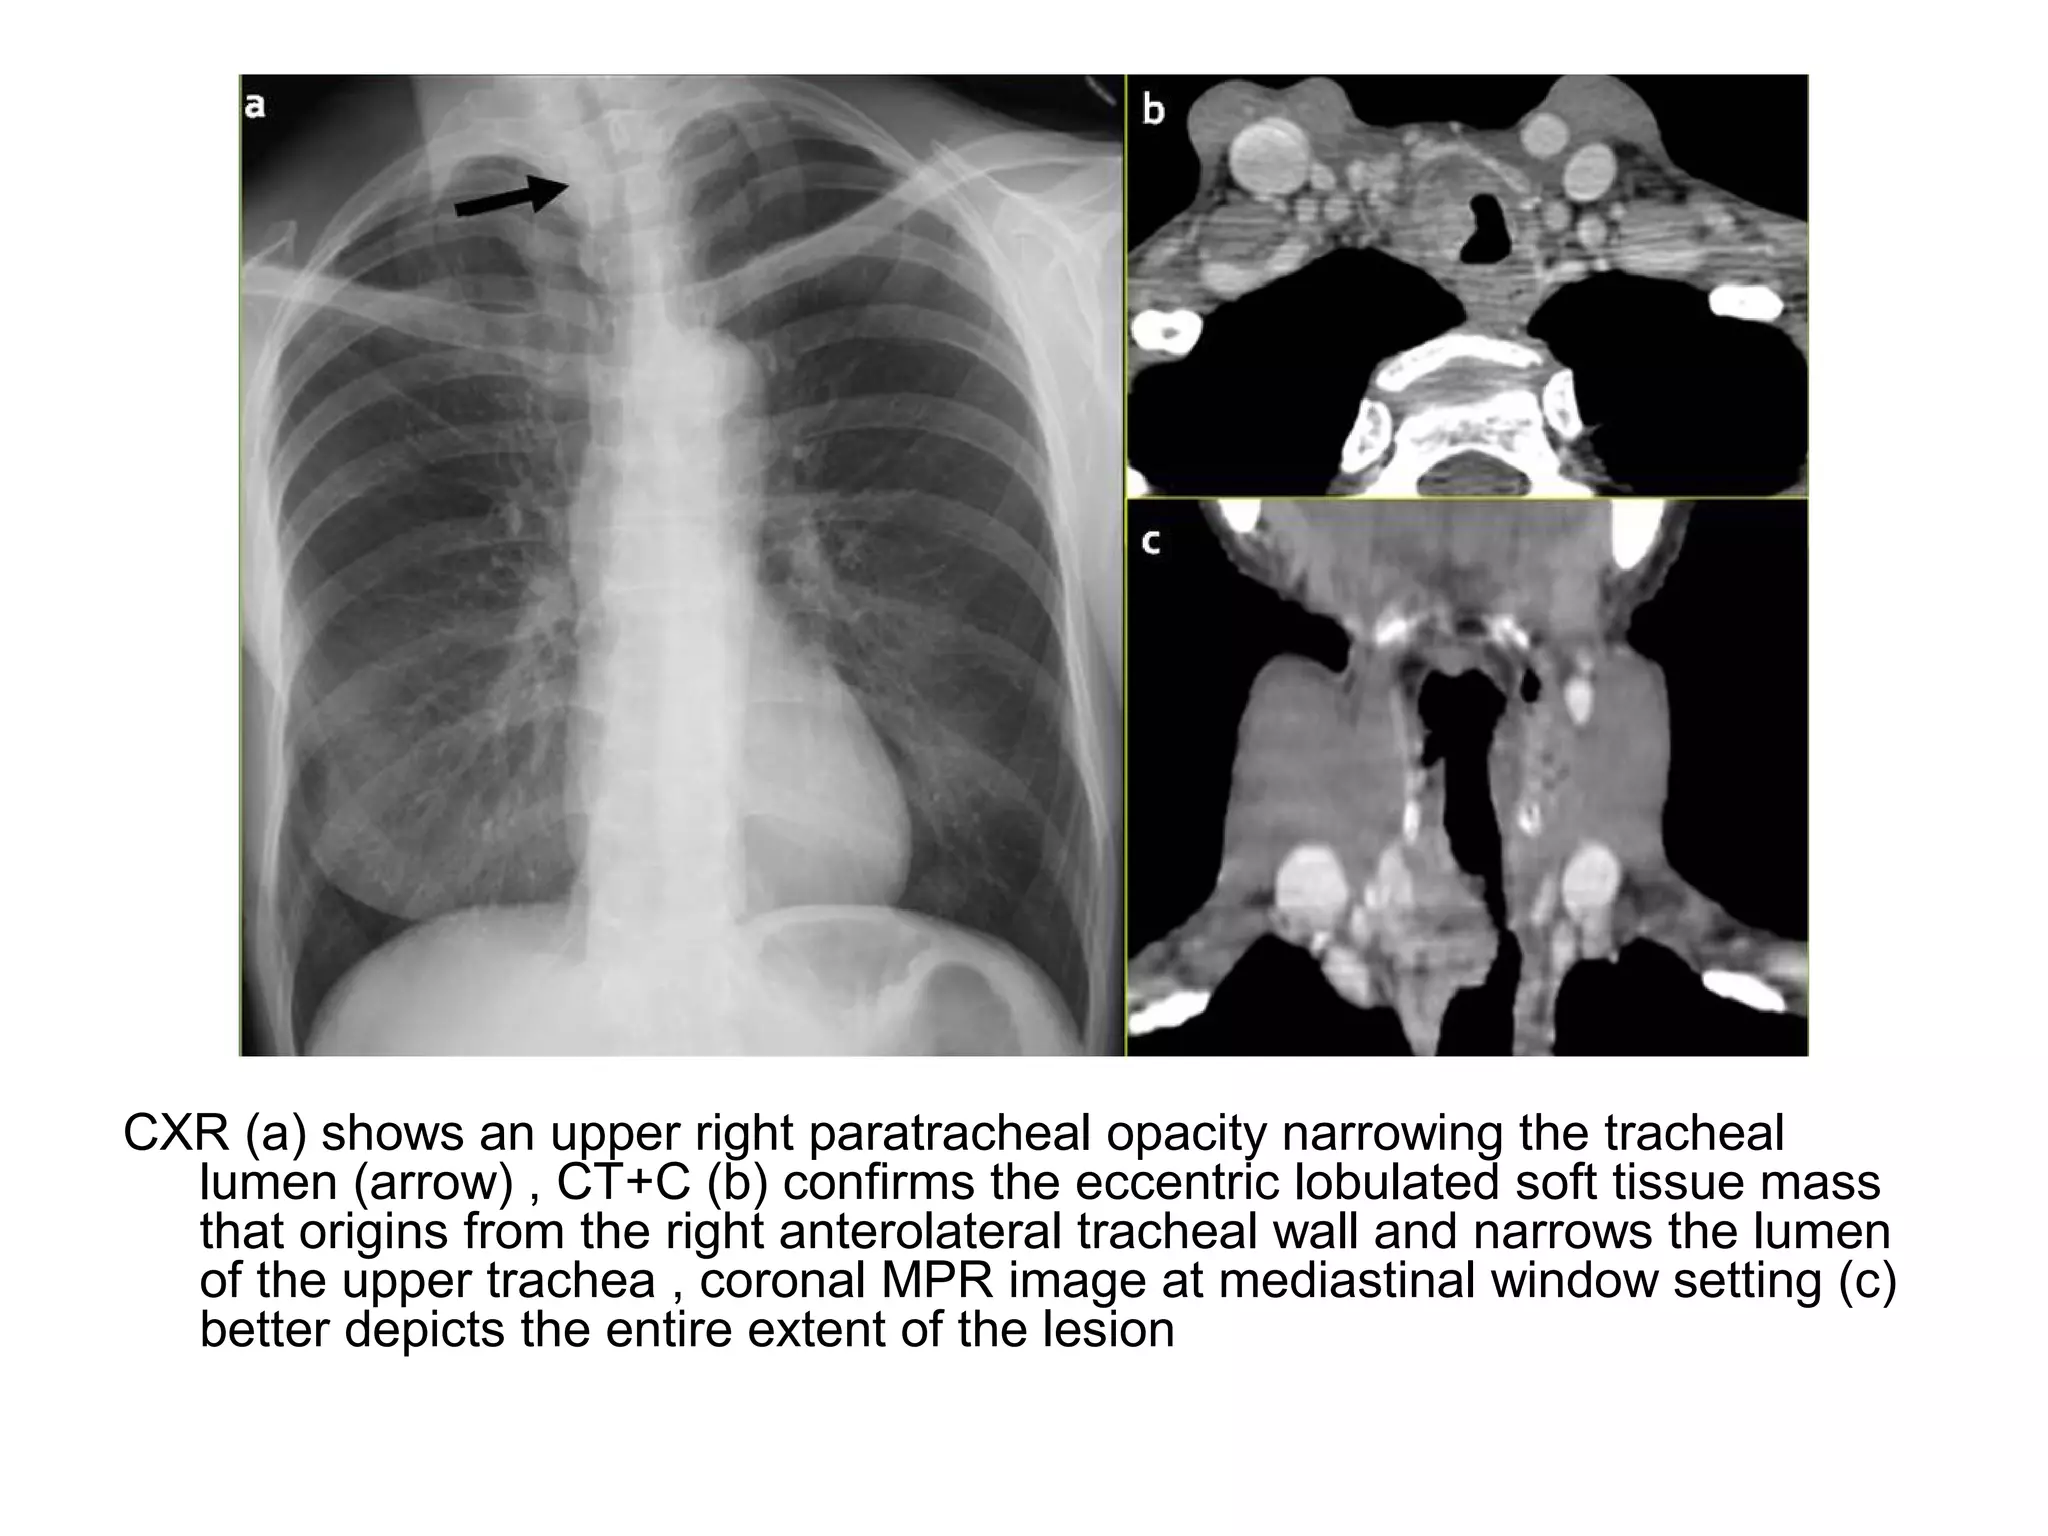

CXR (a) shows an upper right paratracheal opacity narrowing the tracheal

lumen (arrow) , CT+C (b) confirms the eccentric lobulated soft tissue mass

that origins from the right anterolateral tracheal wall and narrows the lumen

of the upper trachea , coronal MPR image at mediastinal window setting (c)

better depicts the entire extent of the lesion